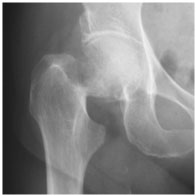

大腿骨頚部骨折 は、全国で年間17万人以上発生しており、高齢化に伴い今後10~20年で年間25万人以上に増加すると予測されています。当院でも手術件数の多い疾患の一つです。大腿骨頚部骨折では、痛みにより歩行が困難になることが多く、原則として手術治療を行います。手術の目的は、骨折部を固定することで痛みを軽減し、早期離床・早期リハビリを可能にすることです。